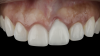

(21.) Eight-month postoperative frontal and occlusal views of the final restorations demonstrating continued stability of the gingival margin and volume.

Figure 21

(22.) Eight-month postoperative frontal and occlusal views of the final restorations demonstrating continued stability of the gingival margin and volume.

Figure 22

A patient presented for the restoration of an implant that had been placed at the site of tooth No. 9, which exhibited a residual soft-tissue deficiency and an undulating facial soft-tissue morphology (Figure 11). The objective of the treatment was to change the appearance and thickness of the facial soft tissue prior to crown placement to optimize the esthetics and prevent future soft-tissue dehiscence. After flap reflection (Figure 12), a graft was acquired from the patient's tuberosity to augment the supracrestal soft tissue (Figure 13). A volume-stable collagen matrix was then placed to further increase the thickness of the soft tissue adjacent to the implant body (Figure 14), and the flap was sutured closed (Figure 15). Following a 3-month healing period, a positive change in the soft tissue's morphology was apparent; however, its volume remained deficient when compared with that of tooth No. 8 (Figure 16). When the screw-retained crown was delivered, a second graft was acquired from the tuberosity and placed to further increase the volume of the supracrestal soft tissue (Figure 17 and Figure 18). A postoperative healing period of 4 months resulted in an ideal position of the margin of tooth No. 9 with regard to its contralateral counterpart as well as more natural looking soft-tissue morphology and excellent supracrestal soft-tissue thickness (Figure 19 and Figure 20). Eight months postoperatively, the position of the gingival margin and the thickness of the soft tissue had been maintained (Figure 21 and Figure 22).